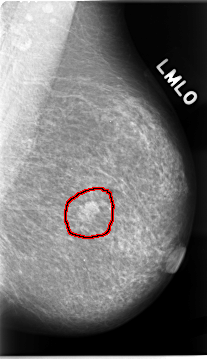

Digital Database for Screening Mammography

Volume: cancer_02 Case: C-0023-1

C_0023_1.LEFT_MLO

LEFT_MLO LINES 4656 PIXELS_PER_LINE 2680 BITS_PER_PIXEL 12 RESOLUTION 50 OVERLAY

FILE: C_0023_1.LEFT_MLO.OVERLAY

TOTAL_ABNORMALITIES 1

ABNORMALITY 1

LESION_TYPE MASS SHAPE LOBULATED MARGINS MICROLOBULATED

ASSESSMENT 5

SUBTLETY 5

PATHOLOGY MALIGNANT

TOTAL_OUTLINES 1

BOUNDARY